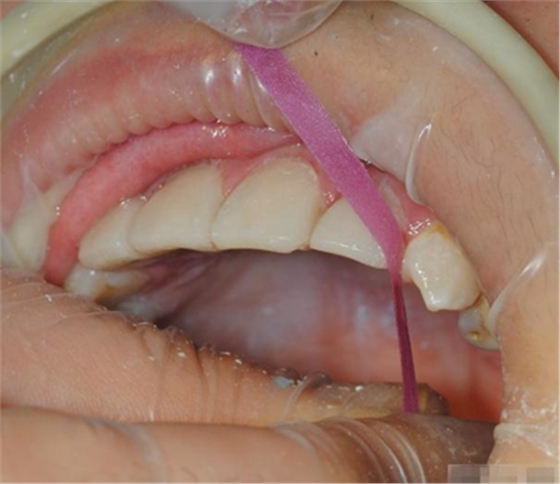

Hawe Sycamore Interdental Wedges——小楓木

切忌在近遠(yuǎn)中同時(shí)放置楔子,這樣會(huì)擠壓牙齒使其伸長,調(diào)合時(shí)會(huì)感覺修復(fù)體過高。如果近遠(yuǎn)中需要修復(fù)時(shí),可在一端放置楔子,修復(fù)后,再放置另一端